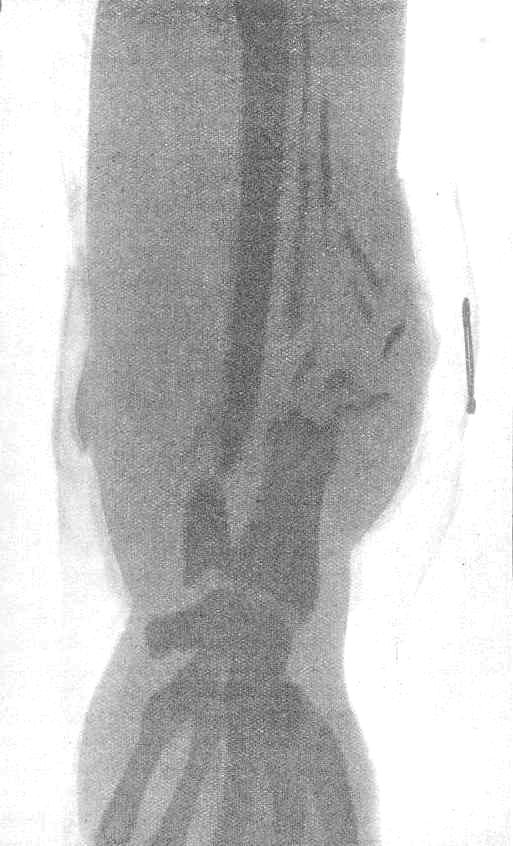

A view of a lower arm in a plaster cast showing a compound comminuted fracture of the radius and ulna. The radius is in fragments and the original trauma was probably a through and through lesion due to a bullet hitting and disintegrating the radius bone. The exit wound was likely to have been on the radial side above the wrist in line with the metallic wire on the surface of the cast.